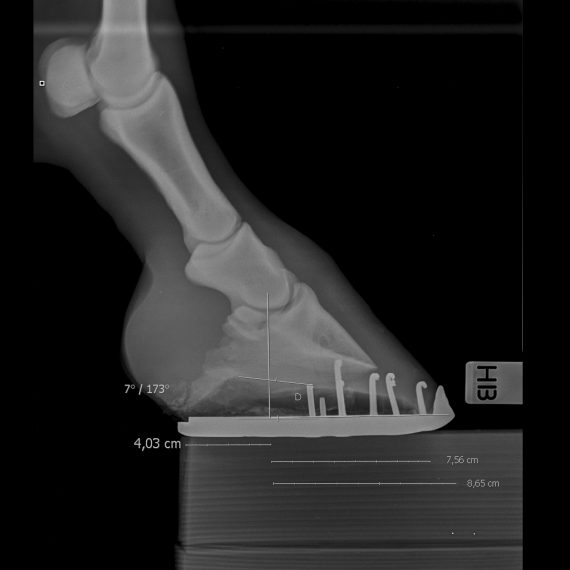

Optimal hovbalanse ved røntgenundersøkelser: Forebygging av halthet

Forståelsen av korrekt hovbalanse er avgjørende for å opprettholde hestens helse og forebygge potensielle skader. Uttrykket «Ingen hov, ingen hest» understreker betydningen av en sunn og godt balansert hov. Ubalanse, feil beskjæring, eller slitasje på hoven kan føre til ufysiologiske belastninger, som igjen disponerer for en rekke lidelser, inkludert leddbetennelser, hovsenebeinsrelaterte plager, og muskulære problemer i rygg og bakpart. Når vi vurderer hoven uten røntgen, søker vi etter en rett linje fra fremsiden av hoven opp til kodeleddet, ideelt sett parallell med baksiden av hoven. Kronranden bør også danne en viss vinkel med underlaget. Røntgen av bakbeinene er like viktig […]

Røntgen er et essensielt diagnostisk verktøy med bred anvendelse, og vi benytter det ved Forus Hesteklinikk for ulike diagnostiske formål: Rutinemessige undersøkelser av unghester: Vi utfører 10 røntgenbilder av hver unghest for å avdekke eventuelle løse biter (OCD), spesielt i hase- og kodeledd. Kjøp/salg-undersøkelser: Vi tilbyr omfattende eller mer begrensede røntgenundersøkelser i forbindelse med kjøp eller salg av hester, tilpasset individuelle behov. Hovbalansevurdering: Korrekt hovbalanse er kritisk for å unngå unødige belastninger på hestens bein, sener, ligamenter, bekken, og rygg. Vi samarbeider med hovslagere for å evaluere hovbalansen ved hjelp av røntgen. Akutte sårskader: Røntgenbilder kan tas av såret for […]